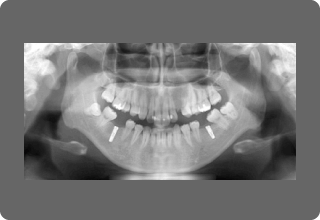

当院では歯科用CTから得られる鮮明な画像から精度の高い診断・安全な治療を行っています。

従来のレントゲンは2次元(平面)の情報のみでしたが、歯科用CTを用いると3次元(立体)の情報を得られ、肉眼で見ただけでは決してわからない顎の骨・歯根の形態、神経の位置などがより正確に把握できます。

一般的な歯科治療はもちろん、インプラントや親知らずの抜歯など外科的な高度治療の診断・シュミレーションにも役立ち、頭部X線規格写真(セファロ)でより精度の高い矯正歯科治療を行うこともできます。

また撮影時間が短く低被曝で、患者さまへの負担も少なく安全です。